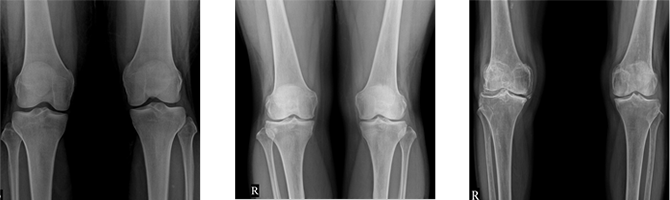

퇴행성관절염 진단

퇴행성관절염은 X-ray를 이용하여 비교적 쉽게 진단이 가능하지만, 고연령자의 경우 어느 정도의 퇴행성 변화는 자연스러운 현상이기 때문에 문진 및 이학적 검사를 종합하여 진단해야 합니다. 또한 증상의 정도와 증상이 지속된 기간 등에 따라 초음파, MRI, 혈액검사 등이 필요할 수 있습니다.

• 정상 X-ray 소견

• 초기관절염 X-ray 소견

• 말기관절염 X-ray 소견